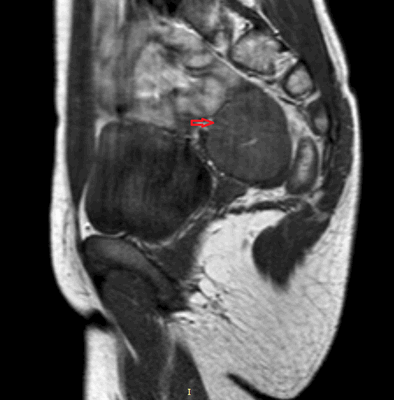

Компьютерная томография органов грудной клетки, брюшной полости, малого таза используются для оценки распространения опухолевого процесса (рис.5).

Рисунок 5. Крестцово-копчиковая тератома у ребенка 2-х лет (МРТ).